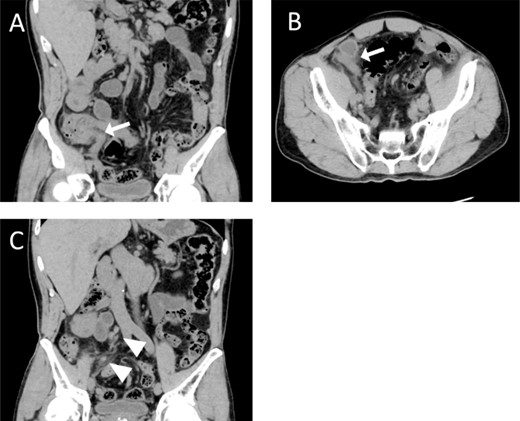

A 65-year-old healthy man presented to the emergency department with persistent lower abdominal pain and vomiting. He exhibited tenderness throughout the lower abdomen, centred on the right lower abdomen, and muscular guarding, with no findings in the upper abdomen. Blood test results showed increased inflammatory findings (white blood cell 17 290/μl, C-reactive protein 0.19 mg/dl), and computed-tomography (CT) showed swelling of the appendix, increased density of surrounding fat tissue, and swollen lymph nodes (Fig. 1). We suspected gangrenous appendicitis and immediately performed laparoscopic appendectomy under general anaesthesia, which revealed perforation at the root of the appendix, indicating localized peritonitis. We performed an appendectomy and intraperitoneal lavage. As the postoperative inflammatory reaction persisted, we continued an antibiotic treatment. The patient was discharged on the 10th postoperative day.

Computed tomography (CT) examination and postoperative pathological examination. Coronal (A) and horizontal (B) views show an enlarged appendix (white arrows). The coronal section (C) also shows enlarged regional lymph nodes (white arrowheads).